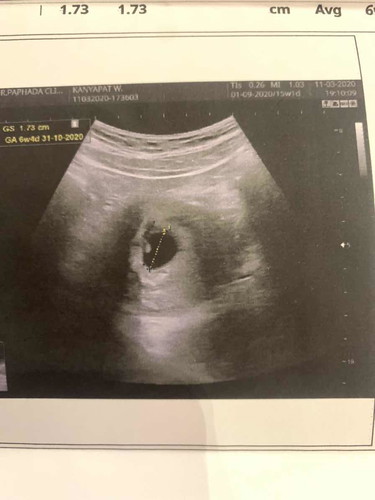

ถ้าเป็นแบบนี้ มีโอกาศท้องลมมั้ยคะ เครียดมากๆ หมอบอก 6W4D ท้องแรกค่ะ หมอทำไมบอก เป็นติ่งๆเล็ก อาจไม่ใช่ตัวอ่อน รออีก 2 วีค?

รอสัก 8-9 วีคลองซาวใหม่นะคะ ตอนซาวตอน6วีคไม่เจออะไรเลยถุงการตั้งครรภ์ไม่มีหมอนัดไปซาวใหม่เจอหมดเลยค่ะ👶